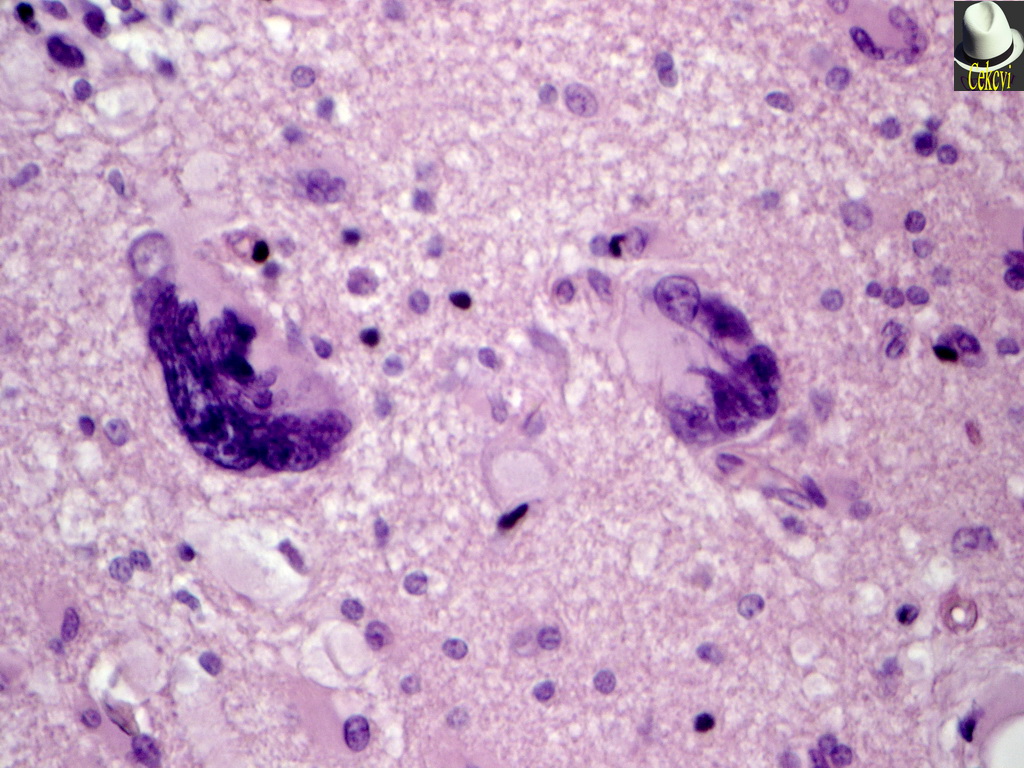

Микрофотографии гистологии глиобластомы головного мозга